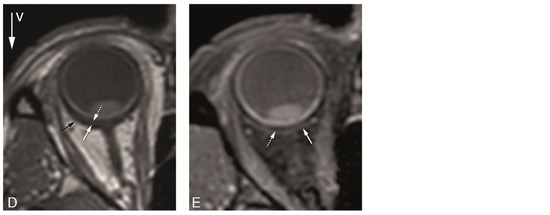

4.2. Anatomical MRI of Uveal Melanoma